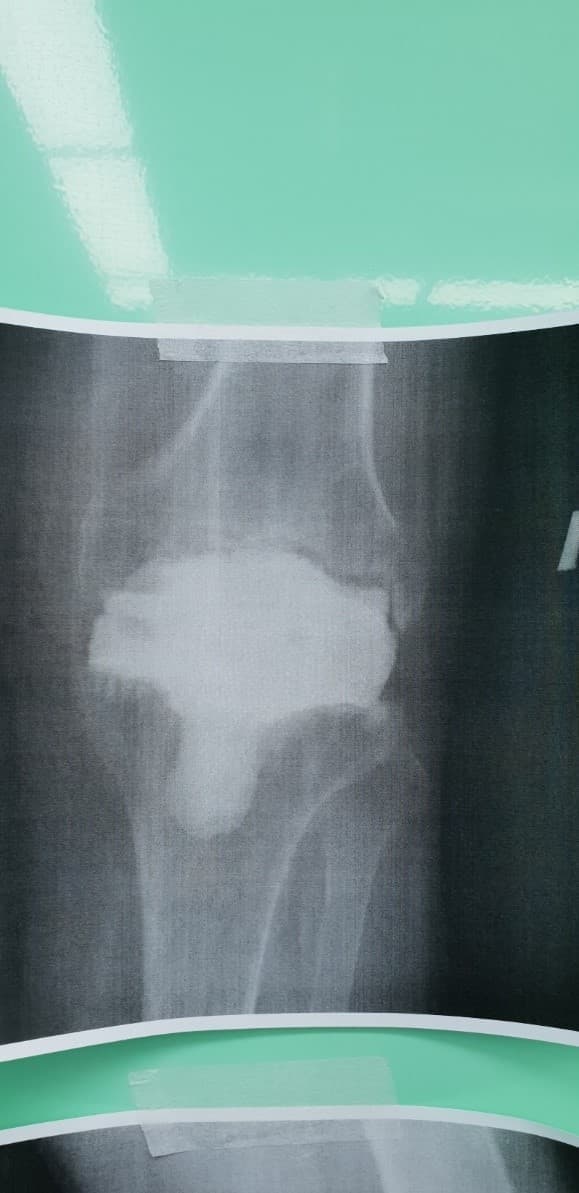

Үе дайрсан ясны анхдагч хавдар, ясны дутмагшлын үед хийгдэх мэс засалimg27Үе дайрсан ясны анхдагч хавдар, ясны дутмагшлын үед хийгдэх мэс засалimg28

Зураг 1. Сэргээн засах мэс заслын өмнөх рентген зураг. Эгц урд, хажуугаас авсан байдал. Халдварын бус шалтгаант хиймэл үений ховхрол.